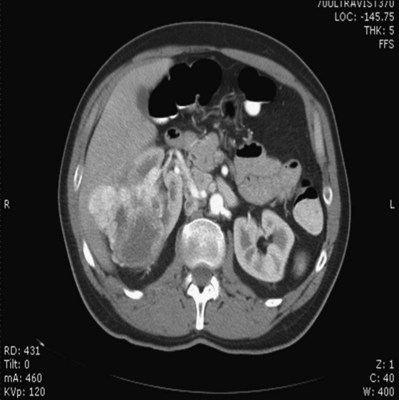

Proposed benefits of preoperative RAE include shrinkage of an arterialized tumor thrombus to ease surgical removal, reduced blood loss, facilitation of dissection due to tissue plane edema, ability to ligate the renal vein before the renal artery at time of nephrectomy, and modulation of the immune response (Klimberg et al, 1985; Bakal et al, 1993; Kalman and Varenhorst, 1999; Schwartz et al, 2007; Wotkowicz and Libertino, 2007; Wszolek et al, 2008). Ligation of the renal vein before the renal artery is useful in the setting of hilar tumors, tumors with significant medial extension, or considerable perihilar adenopathy (Schwartz et al, 2007; Wotkowicz and Libertino, 2007; Wszolek et al, 2008). Before ligating the renal vein, one should characterize the completeness of embolization to prevent unnecessary blood loss in cases of incomplete embolization. In the senior author’s experience this assessment can be made by evaluating renal venous return during surgery. In addition, angioembolization can also be useful for renal tumors associated with large arteriovenous malformations that are having a deleterious hemodynamic impact (Figs. 54-16 and 54-17).

Figure 54–16 Noncontrast (A) and contrast-enhanced (B) CT images of a patient with high output cardiac failure secondary to arteriovenous malformation associated with left renal cell carcinoma. Notice the equal contrast intensity of the aorta, left renal artery, and left renal vein.

Figure 54–17 A, Left selective renal angiogram demonstrates immediate filling of the renal vein and inferior vena cava. B, Angiogram after placement of coils demonstrates complete angioinfarction. Contrast medium in the contralateral renal pelvis confirms contralateral renal function.